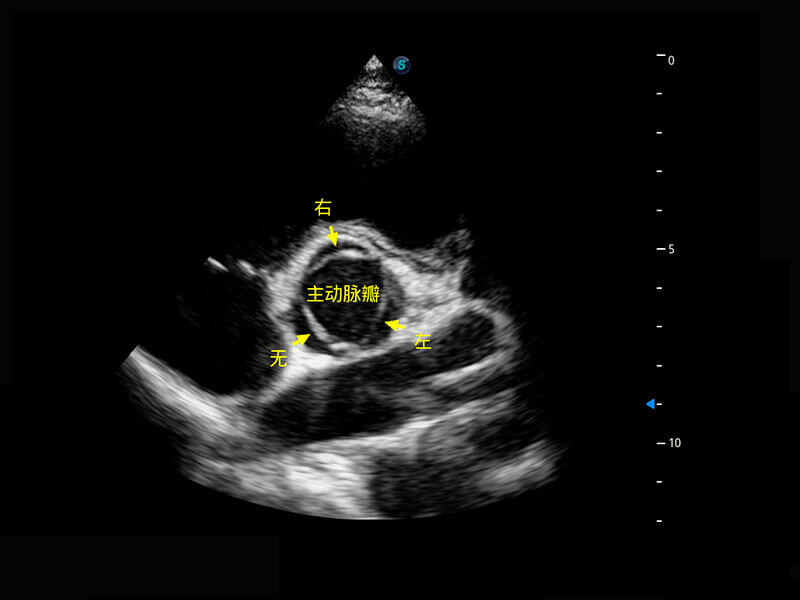

胎心筛查

P60搭载一系列胎儿心脏成像技术,实现精细的胎儿心脏评估。

• 四腔切面

• 四腔心血流

• 右室双出口

• 胎心容积成像

• 新生儿心脏